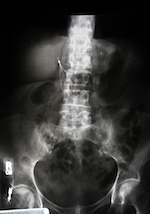

The Greenfield™ filter is implanted in patients’ veins to stop current blood clots from traveling while maintaining as normal a blood flow as possible. According to the manufacturer website, more than one million of these devices have been implanted in the last three decades.